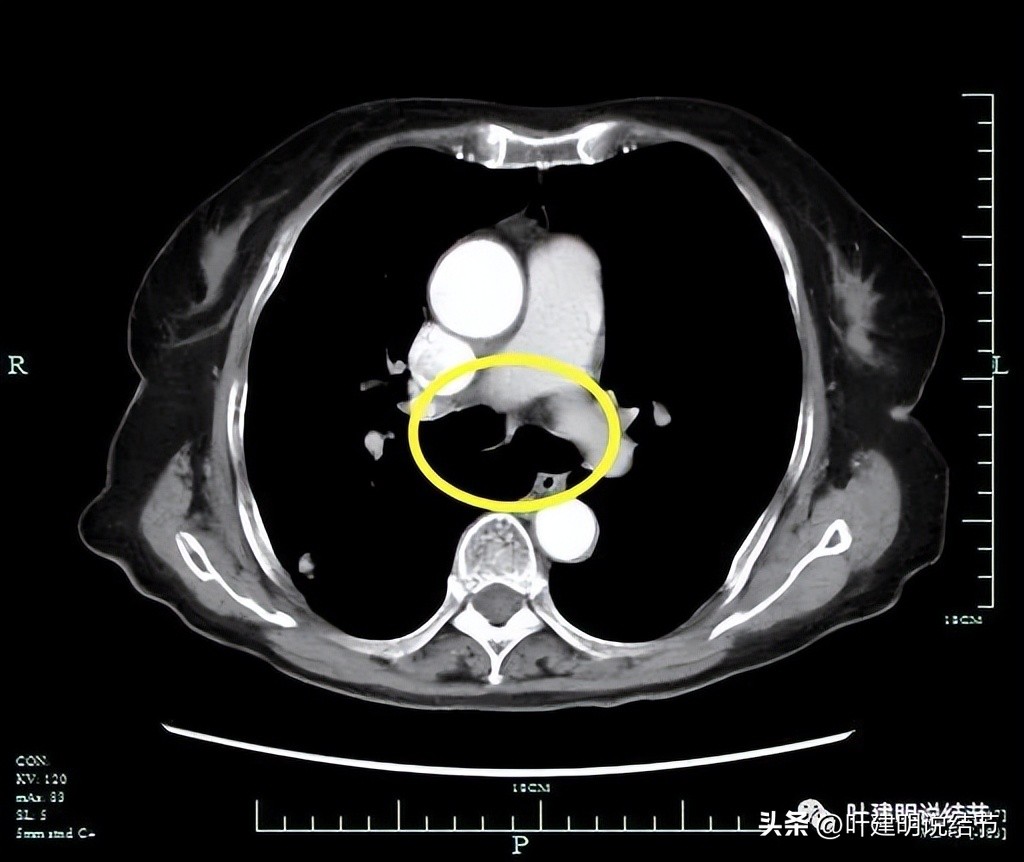

上图是PET-CT怀疑转移的淋巴结,跨在肺动脉上(跨在尖前干的上方)

隆突下未见明显肿大淋巴结。